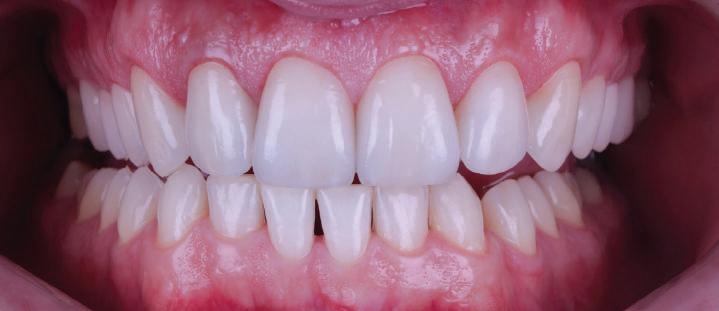

Една седмица след препарацията на зъбите и циментирането на цирко ниевото кепе бяха изработени 12 IPS Empress Cad Multi фасети. Макро- и микротекстурата на фасе тите бяха направени на ръка, след кое то бяха нанесени 3D характеризации с боички, а полирането отново бе напра вено ръчно, за да им се придаде естест вен и естетичен вид. Предизвикателството тук беше короната да има същите оптични характеристики като тези на остана лите зъби при естествена светлина, през поляризационен и флуоресцентен филтър. 3D принтерът бе Fromlabs, софтуерът за фрезоване – Mill Box, а фрез апаратът –imes icore CORiTEC 350i. В крайна сметка постигнахме ес тествен вид на усмивката с натурал на зъбна морфология при изцяло диги тален протокол, при който дизайнът бе направен първоначално и през всич ки етапи на лечението се придържахме към него до самия край Излишно е да отбелязваме, че всички сме удовлетворени от постигнатото! Преди След Победител в категория „Клиничен случай с изцяло дигитален протокол“ в конкурса „Усмивка на годината 2022“

13Dental Tribune Bulgarian Edition / октомври 2022 г. След лечението За авторите: Д-р Калин Маринов е специалист в областта на имплантологията, протетиката и естетичната хирургия. Завършил е дентална медици на в София през 2012 г. През 2014 г. основава Sky Dental Clinic. Бил е на обмен ни начала в катедра „Протетика“ на Университета по дентална медицина във Фрайбург, Германия. Живял е и е практикувал в Мелбърн, Австралия, и е посеща вал курсове и лекции в Италия, Швейцария, Германия с насоченост в естетич ната хирургия и имплантология, както и тоталната рехабилитация на устна та кухина чрез импланти. Зт. Стефан Петров основава собствена лаборатория през 2006 г. Официален демонстратор на GC за България, като от 2015 г. е KOL за Източна Европа. Инструктор е на Straumann за България. Лаборатория та му има сертификат за пилотна лаборатория на Micerium – Италия. Носител е на множество награди в денталния конкурс „Усмивка на годината”. Носител е на награда CERAMISTS MASTER CUP с д-р Софиен Риахи в престижния международен конгрес CERAMISTS – NO LIMITS 2015 г. Изнася лекции и провежда курсове в редица европейски страни. Фиг. 37 Фиг. 40 Фиг. 43 Фиг. 45 Фиг. 47 Фиг. 50 Фиг. 48 Фиг. 49 Фиг. 41 Фиг. 44 Фиг. 46 Фиг. 42 Фиг. 38 Фиг. 39

Пациентът постъпи в клиниката с молба за тотална рехабилитация на усмивката. Той не харесваше централ ните си резци, които според него бяха твърде къси и квадратни. Имаше раз стояние от медиално и дистално на латералните му резци. Друго сериоз но оплакване бе свързано с металоке рамичната корона на зъб 12, която бе жълтеникава и неестетична, като цяло не харесваше вида на венците си и както самият той се изразяваше, „вижда се прекалено много от венците при усмивка“.